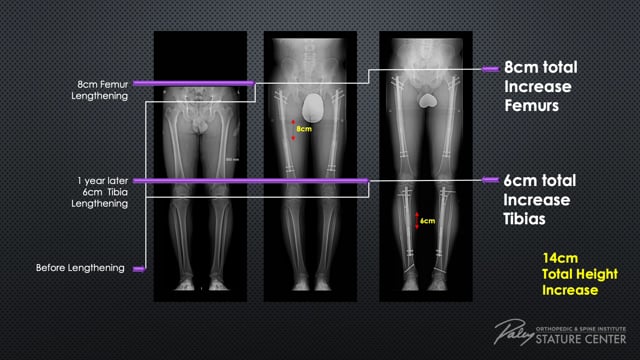

IM NOT DOWNPLAYING LL, BUT THE ONLY PLACE TO ACTUALLY GET IT WITHOUT GETTING BOTCHED IS PALEY

4k patients no recorded botches which is crazy impressive

Stature Lengthening Surgery Options - Paley Stature Center

Paley Orthopedic & Spine Institute offers five lengthening options to get maximum height with each lengthening.